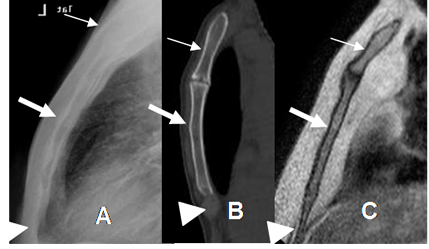

Fig 3. Esternón normal.

A: Rx lateral. B: TAC reconstrucción sagital y C: RM sagital en T1. Esternón normal. Manubrio (Flecha delgada), cuerpo (Flecha gruesa) y apéndice xifoides. (Punta de flecha).